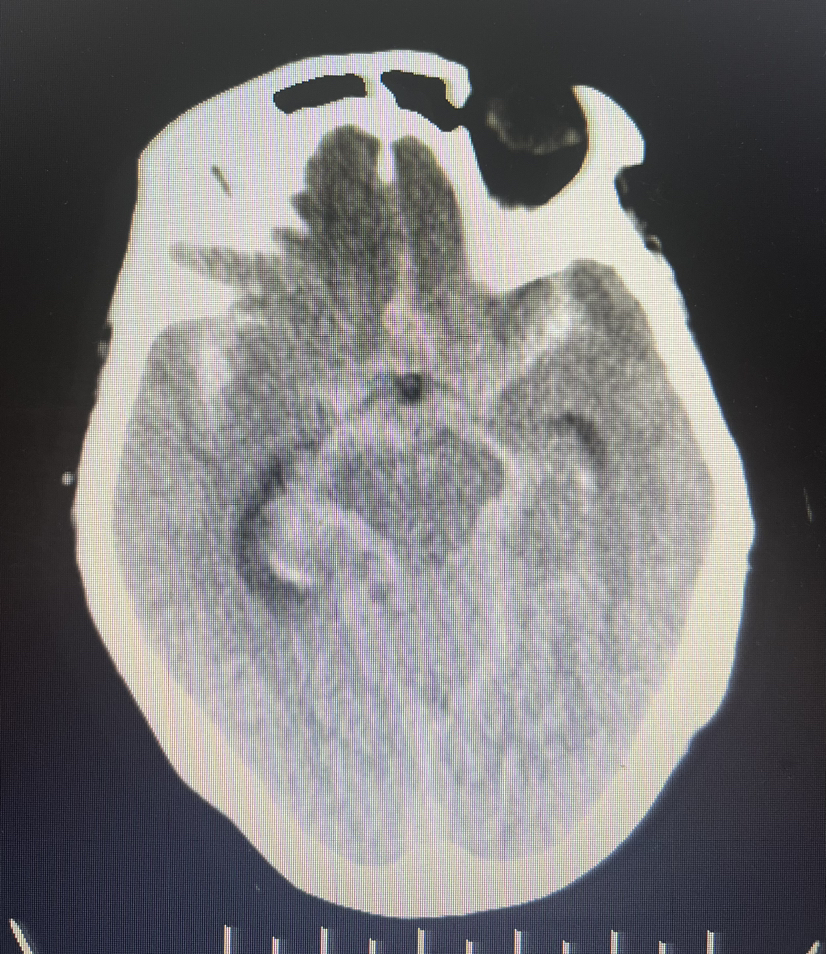

4、急诊CTA:

DSA:双侧大脑前动脉A1段存在,右侧A1段与前交通动脉结合处囊状凸起,最大径约2.8m m